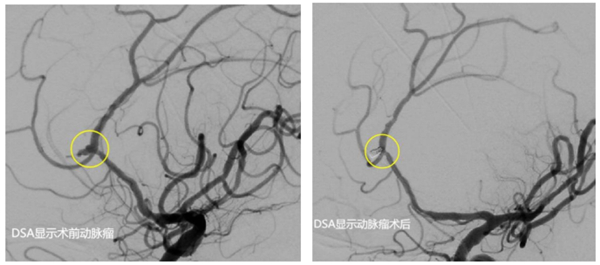

由于患者顱內(nèi)動(dòng)脈瘤破裂出血量極大,已陷入深度昏迷,Hunt-HessⅤ級(jí),病情危重,時(shí)間緊迫。醫(yī)生向患者家屬告知病情,并建議盡快手術(shù),將出血的動(dòng)脈瘤進(jìn)行栓塞,防止再度出血。

經(jīng)和家屬協(xié)商,同意進(jìn)行手術(shù)。該院神經(jīng)外科介入團(tuán)隊(duì)立即啟動(dòng)手術(shù)預(yù)案。麻醉醫(yī)師、手術(shù)室護(hù)士、導(dǎo)管室醫(yī)護(hù)等提前做好術(shù)前準(zhǔn)備。麻醉成功后,先行腦室鉆孔引流,為動(dòng)脈瘤栓塞爭取更多時(shí)間。而后,順利找到了破裂出血的動(dòng)脈瘤并完美致密填塞,出血情況得到控制。歷經(jīng)4個(gè)小時(shí)的救治,最終將患者從死亡邊緣拉了回來。